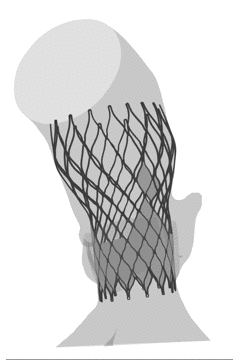

FEops量化评估瓣周漏

根据FEops评估报告得知,L26号瓣膜在高位和标准位释放之后几乎没有瓣周漏,所以两种释放位置都可以考虑。

L26号瓣膜高位植入后的瓣周漏

L26号瓣膜标准位植入后的瓣周漏